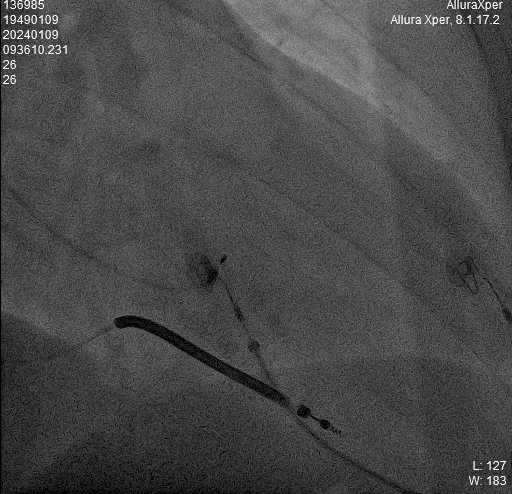

LBB影像位置

术中影像 HIS-HISD-消融靶点

另外,在手术演示间隙的MINI TALK环节中,复旦大学附属中山医院陈学颖教授讨论了损伤电流在左束支起搏术中的应用价值。同时,江苏省人民医院侯小锋教授对左束支起搏术中的起搏测试进行了精彩的演讲。此外,温州医科大学附属第一医院苏蓝教授则对如何选择右室面拧入点做了详细说明。这些讨论和演讲内容丰富,对手术操作具有重要指导意义。